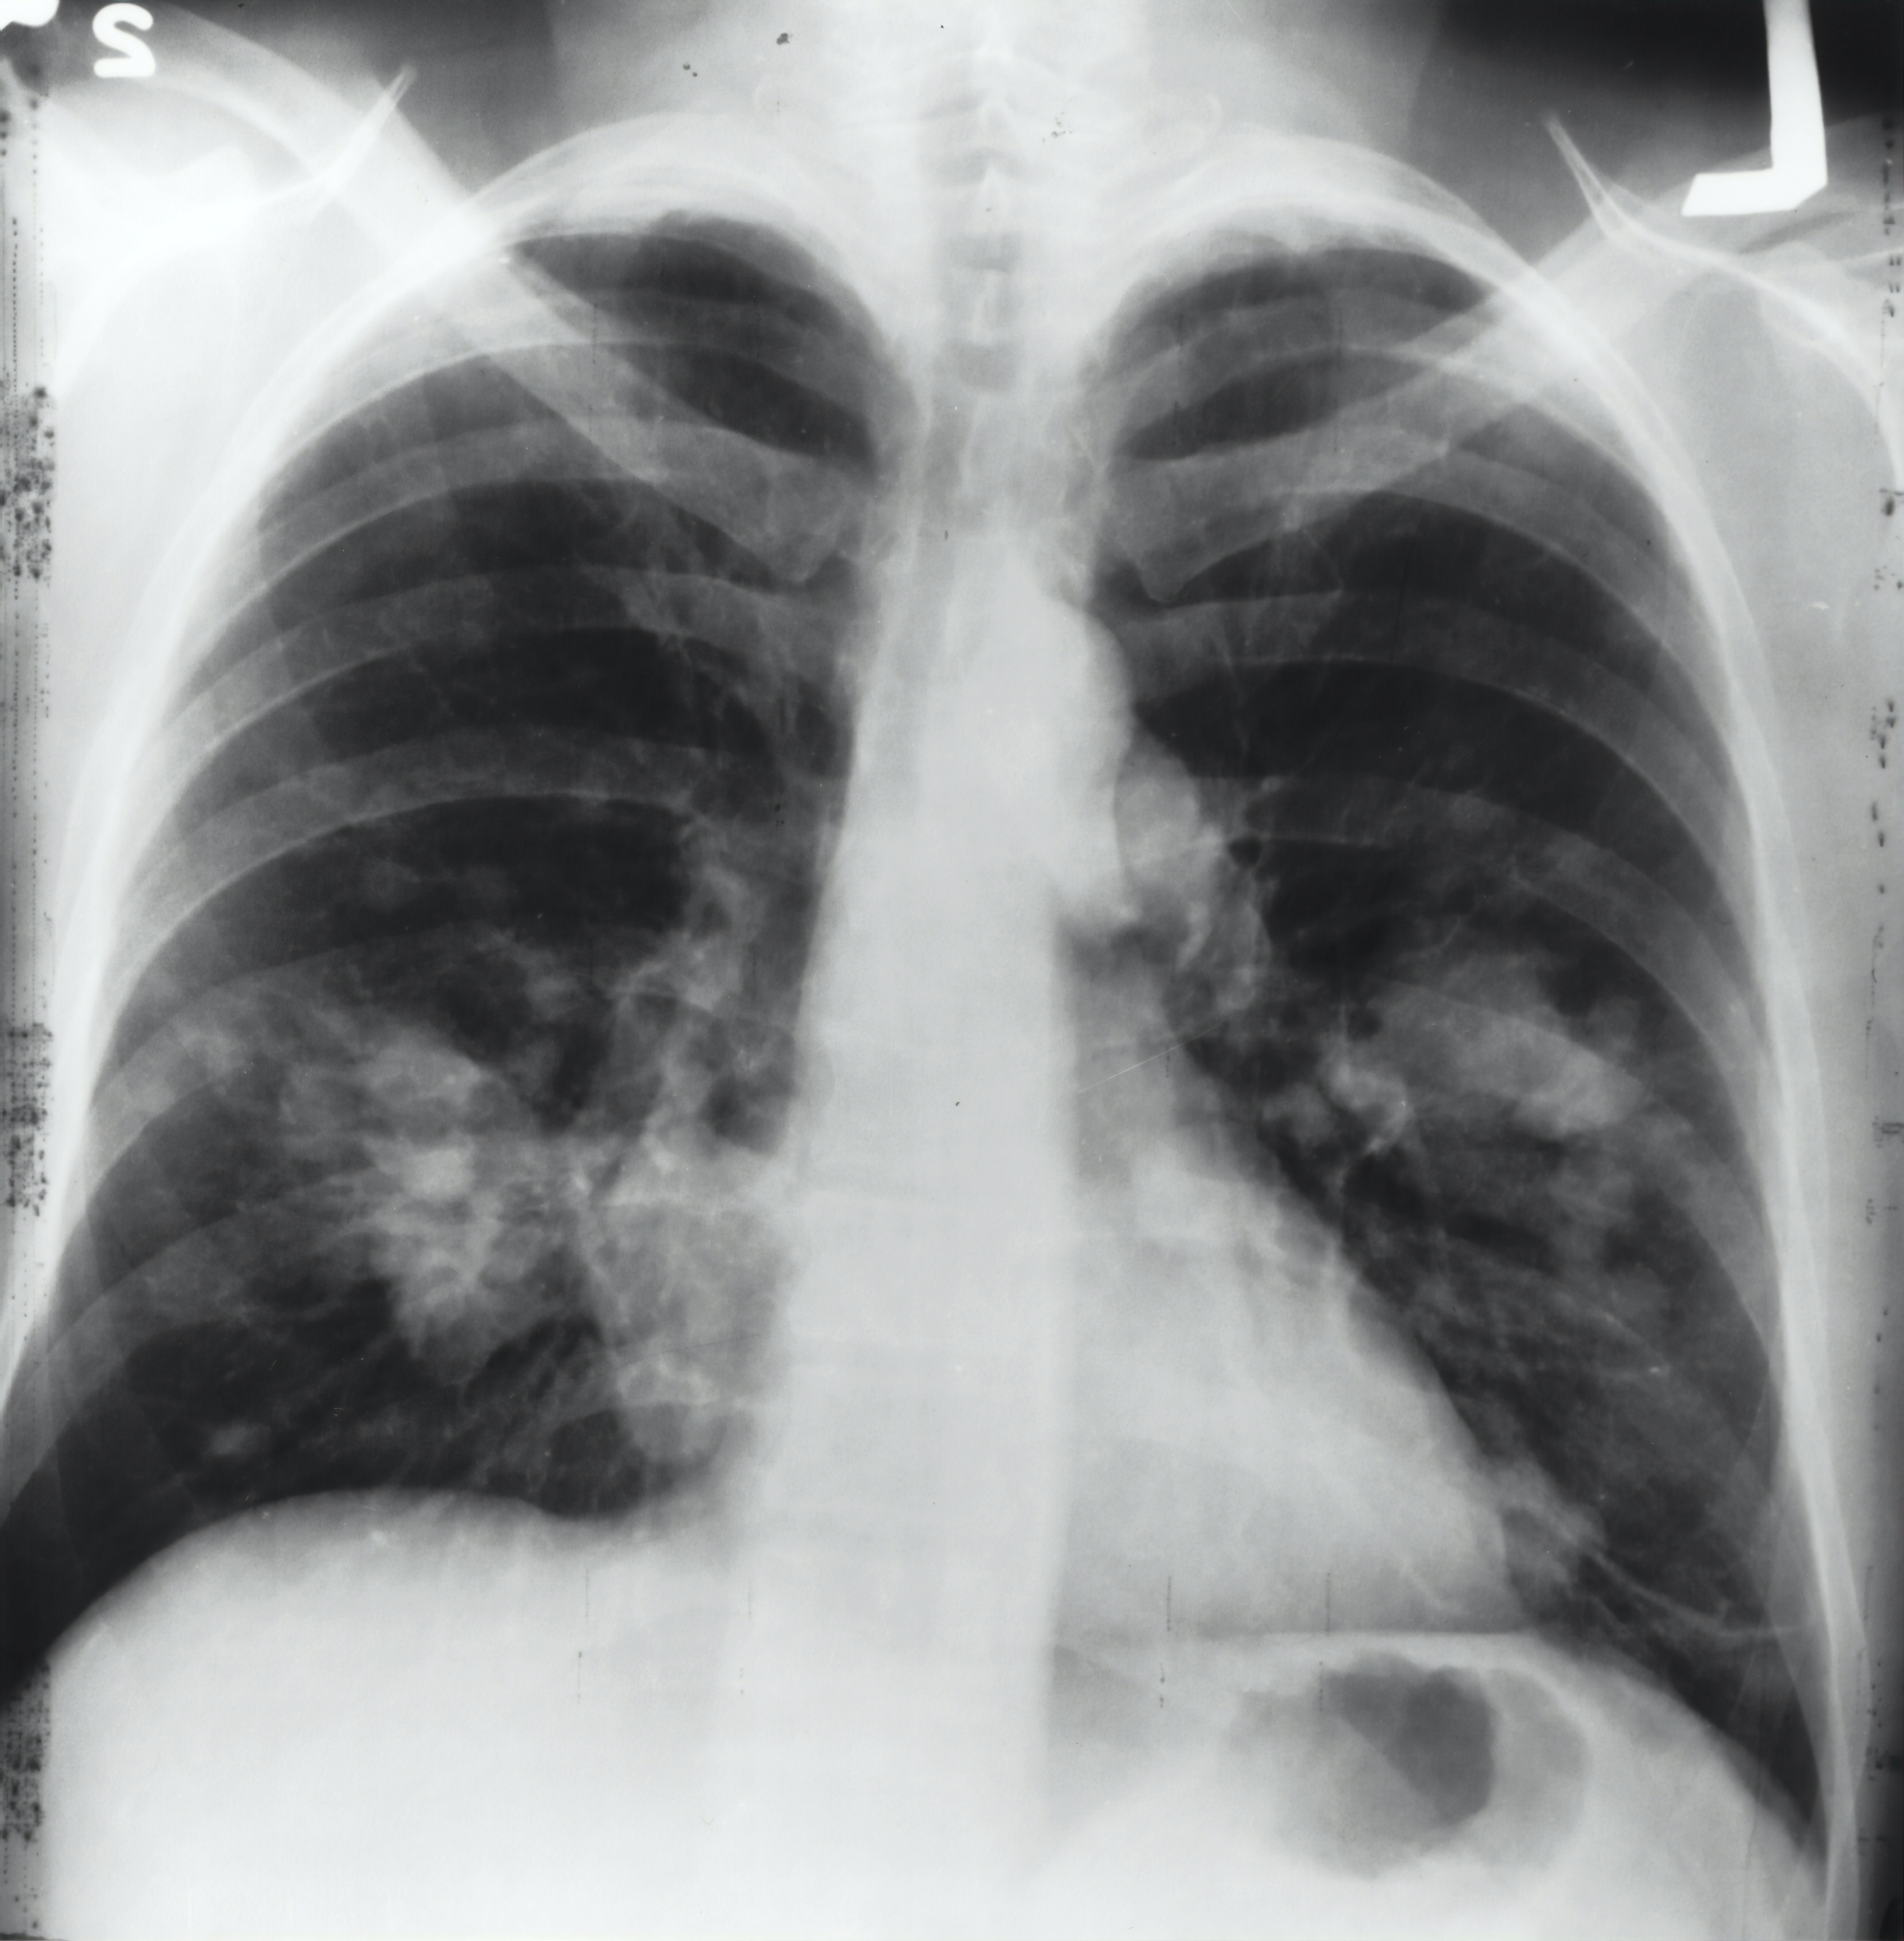

After the tears and the initial shock of the diagnosis, all that was in my mind was, “How did this happen? How could we have missed this?” “I’ve had medical reviews before, how did the x-rays not show, and the tumours grow to such a large size?” The questions were relentless in my mind but after talking to friends, we realized no amount of questioning was going to do any good at this point.